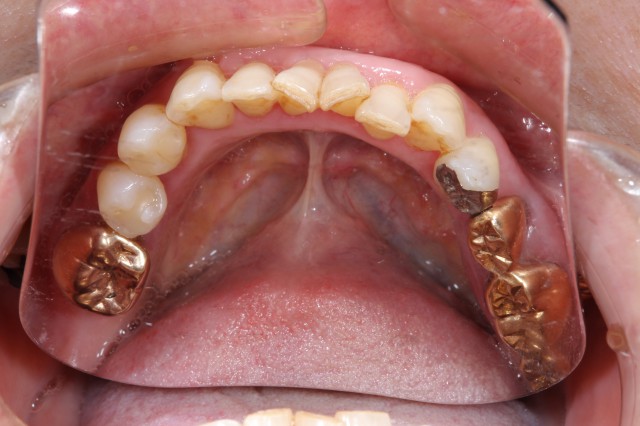

施術前

施術後